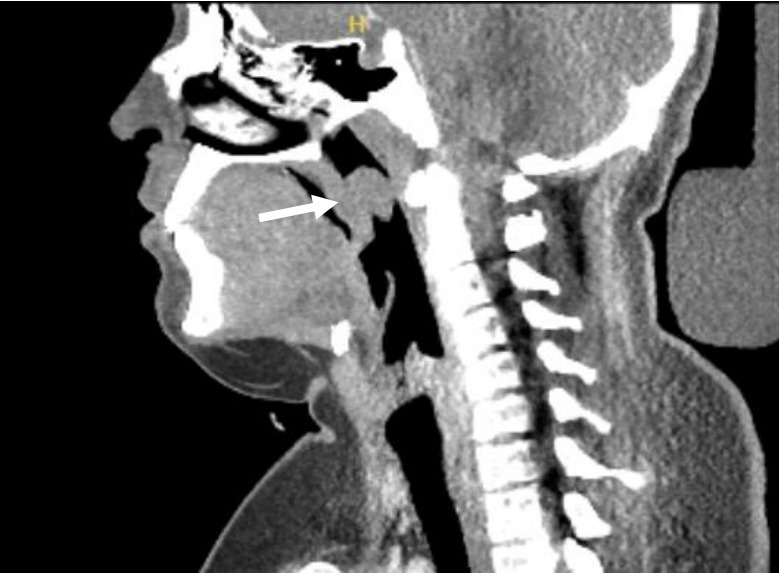

Adenomatous polyposis coli (APC) is a tumor suppressor gene expressed throughout the body. APC mutations increase the risk of malignancy and are often characterized by syndromes that encompass a spectrum of neoplastic manifestations, such as familial adenomatous polyposis (FAP). We present a rare case of palatal peripheral nerve sheath tumor in the context of APC gene mutation. A 17-year-old male with a significant history of FAP presented to our clinic with globus sensation for 5 months with increasing discomfort. Flexible nasolaryngoscopy revealed a pedunculated lesion attached to the posterior surface of the soft palate. Imaging was obtained and confirmed a soft tissue homogenous mass contiguous with the soft palate. Endoscopic-assisted transoral resection was performed and pathologic features were consistent with schwannoma. We also discuss the spectrum of benign neoplastic lesions. Current literature fails to describe pharyngeal masses in the setting of APC gene mutations. The purpose of this case report is to describe a patient presentation of a symptomatic pharyngeal tumor with a known APC gene mutation and explore the differential diagnoses that must be considered.